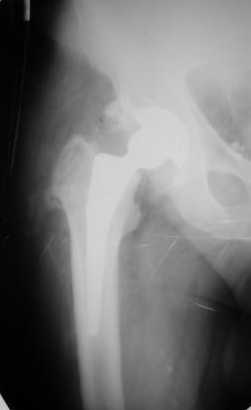

Больной Т. 56 лет, Диагноз: двухсторонний коксартроз 3-4 ст справа, 1-2 ст слева 2.10.08 выполнена операция тотальное бесцементное эндопротезирование. Использовался наружный доступ, положение на боку. Операция протекала без особенностей.

Выполнен послеоперационный ренгеноконтроль в прямой проекции. Рана зажила.

Уважаемый Глеб, предложенные снимки впечатлили! Никто не застрахован...

Приходилось ли кому встречаться с такой ситуацией?Вопросы: вросла ли ножка? Какие могут возникнуть сложности с удалением ножки? Нужна ли будет дополнительная трепанация диафиза? И как? Правильный выбор ножка Corail для ревизии в такой ситуации?